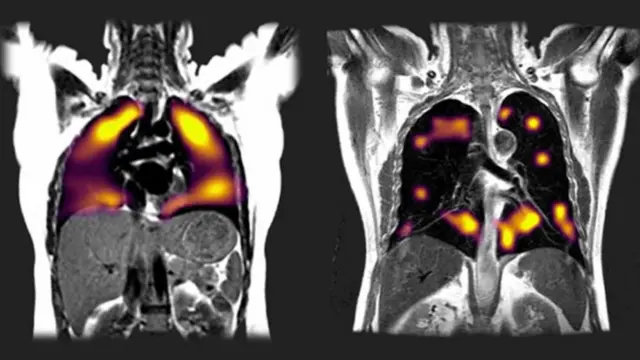

İngiltere'de geliştirilen yeni bir manyetik görüntüleme tekniği ile, Covid-19 teşhisi konan hastaların akciğerlerinde teşhisten üç ay sonra bile bazı anormallikler tespit edildi.

Oxford Üniversitesi'nde 10 hasta üzerinde yapılan araştırmada, yeni bir tarama tekniği kullanılarak, normal taramalarda tespit edilemeyen akciğer hasarlarına rastlandı.

Bu yeni tarz EMAR'da (manyetik rezönans görüntüleme) ksenon (zenon) gazı kullanılarak akciğerdeki hasarın kapsamı tespit ediliyor.

Bunların sekizi, yoğun bakıma kaldırılmamış ve solunum cihazına bağlanmamış olmalarına rağmen, koronavirüse yakalanmalarının üzerinden üç ay geçtikten sonra bile nefes darlığı ve yorgunluktan şikayet ediyordu. Normal taramalarda akciğerlerinde herhangi bir soruna rastlanmamıştı.

Ksenon gazıyla yapılan taramalarda ise bu hastalarda akciğer hasarı belirtilerine rastlandı. Kana rahat oksijen akışı olmayan bölgeler tespit edildi.

Gleeson, taramalar sonucunda hastalarda ortaya çıkan hasar boyutunun beklediklerinden fazla olduğunu kaydetti.

Kaynak, OXFORD ÜNİVERSİTESİ